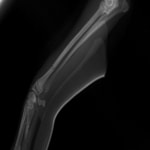

症例3:キルシュナーワイヤーのピンニングによる整復

ペルシャ猫 11ヶ月齢 雄

他院にて左大腿骨遠位の成長板骨折(salter-harrisⅠ型)が認められており、治療相談を目的として来院。当院にて、キルシュナーワイヤーを用いたピンニングにより骨折部位の整復を行いました。術後の経過は良好で、現在も経過観察中です。

術前レントゲン

術後レントゲン